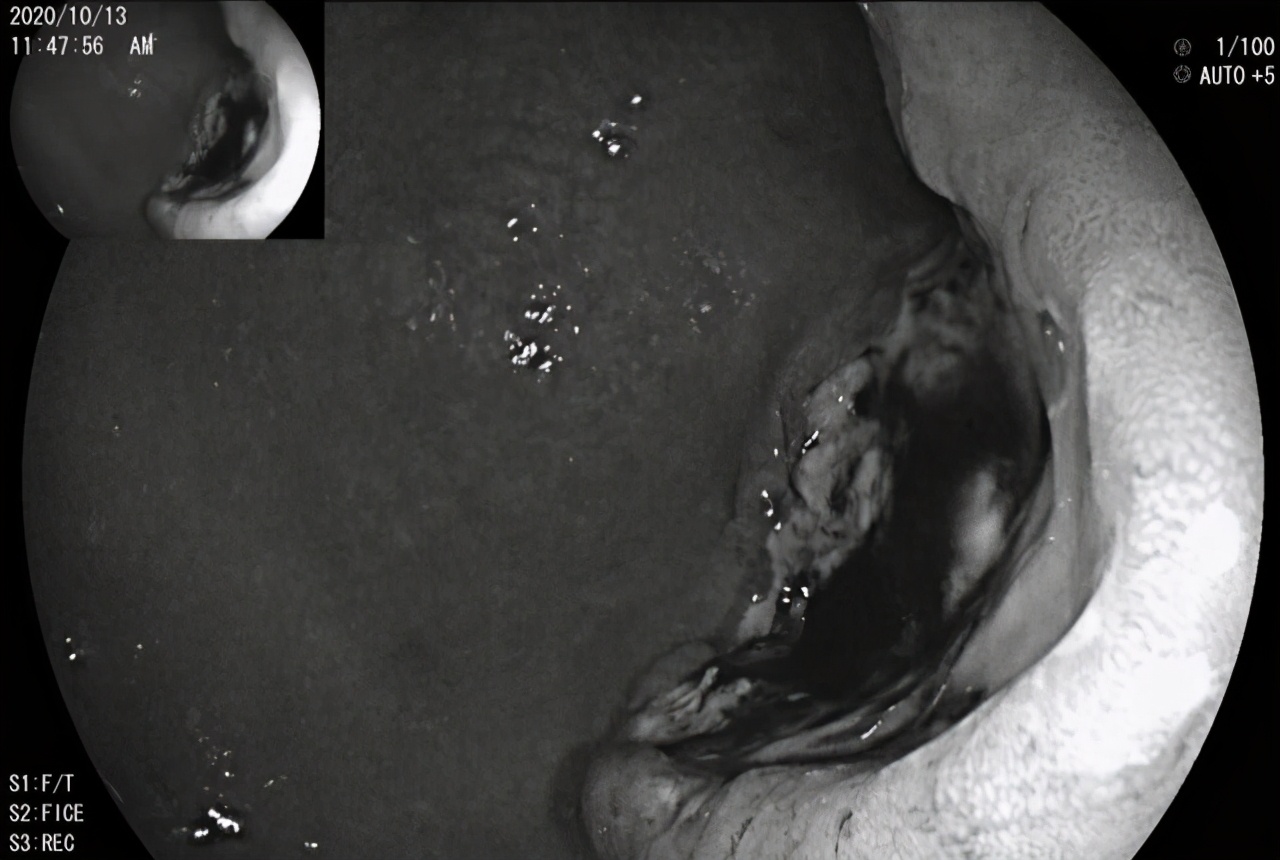

我进镜刚看到胃窦,一个巨大的溃疡性病灶,就呈现在眼前!

底部不光滑、污秽苔、黑色血痂,周边粘膜隆起,质地硬,易出血,绝非善类!

我想,坏了,这个溃疡长这个样子,质地这么硬,胃癌!